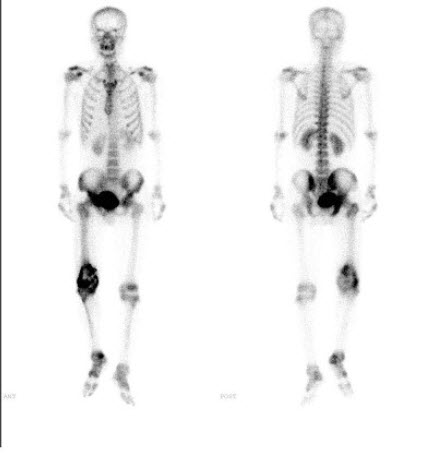

40、单项选择题

男,32岁,双侧上肢疼痛3个月,有慢性肾炎病史,无发热、无外伤及肿瘤病史,行全身骨显像如图,最可能的诊断是()

A.骨纤维结构不良

B.肾性骨营养不良

C.Paget病

D.双侧上肢骨转移癌

E.以上都不是